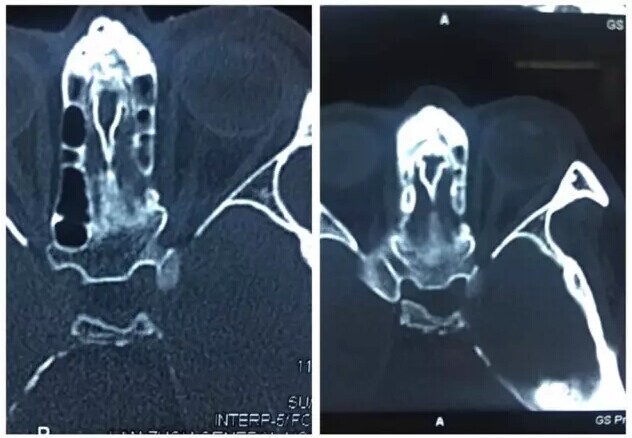

甘肃省二院眼科开展经眼眶视神经减压术使许多外伤失明的患者重见光明------2017-04-28 发布时间:2017-04-28 来源: 作者:

本文转自:薛尚才团队